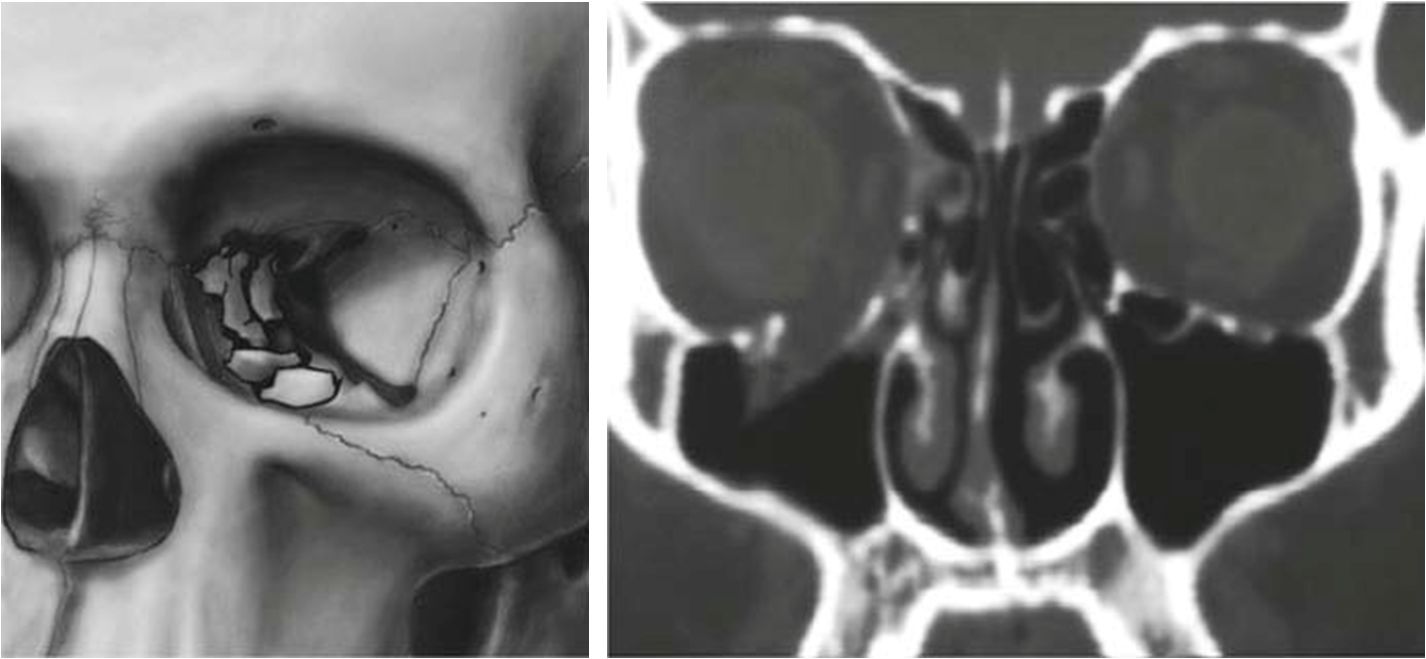

眼眶骨折是常見的顱頜面損傷類型之一,可單獨發(fā)生,也可與顱面其他骨折聯(lián)合發(fā)生。眼眶對眼球起到保護作用,眼眶或眼眶周圍骨骼遭受外力打擊,可出現(xiàn)眼眶骨折。